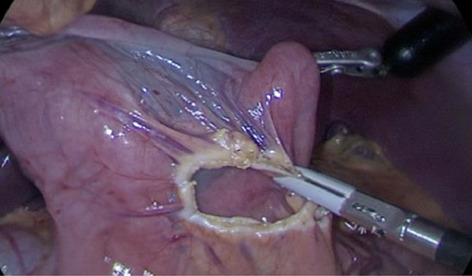

Introduction: Minimally invasive surgery and lately the usage of robotic technology has reduced the invasiveness of procedures, leading to improved patient outcomes after esophagectomy. The esophagogastric anastomosis represents a crucial step of the Ivor-Lewis procedure, as technical errors may lead to anastomotic leakage and severe postoperative morbidity. Anastomotic integrity is influenced by many different factors and there is great technical variety among surgeons. We have previously shown that a standardized 28-mm circular stapled anastomosis is very safe in Hybrid Minimally Invasive Esophagectomy. The aim of this study was to present and evaluate our standardized robotic circular stapled anastomotic technique in comparison to our large Hybrid patient collective.

Methods: Analysis of our prospectively collected, IRB approved database of hybrid, open, and robotic esophagectomies was performed. Starting 01/2019, we implemented an updated robotic standardized anastomotic technique using a circular stapler and ICG (indocyanine green) for our RAMIE cases at our academic center (Picture 1). Outcomes of patients undergoing this standardized robotic Ivor Lewis esophagectomy for esophageal cancer from 01/2019 – 11/2020 were compared to our overall cohort from 06/2016–06/2020 (Hybrid/Open group).Propensity score matching comparing robotic to hybrid procedures will be performed and data will be presented upon the meeting.

Results: A total of 615 patients were analyzed. A total of 96 patients underwent a robotic assisted Ivor Lewis esophagectomy. Of these, a total of 56 patients underwent a robotic thoracic reconstruction using the updated standardized circular stapled anastomosis. A total of 64 patients were operated using an open approach and 455 underwent a hybrid procedure with a circular stapled anastomosis (Hybrid/Open group). Demographic and oncological data is shown in Table 1. Mean age was 63 years (range 46–80) in the robotic group and 63 years (range 33–91) in the hybrid/open group. Further details about postoperative complications are depicted in Table 2. One patient developed an anastomotic leak in the robotic group, resulting in an anastomotic leak rate of 1.8%. In comparison 63 patients (12%) developed an anastomotic leak in the Hybrid/Open group (p = 0.0132). Median length of stay (LOS) was 13 days in the robotic group (range 7–52), compared to a median LOS of 15 days (range 9–99) in the open/hybrid group.

Conclusion: A standardized circular stapled anastomosis in RAMIE cases for esophageal cancer may result in very low anastomotic leak rates and thereby positively influence outcomes in selected esophageal cancer patients.